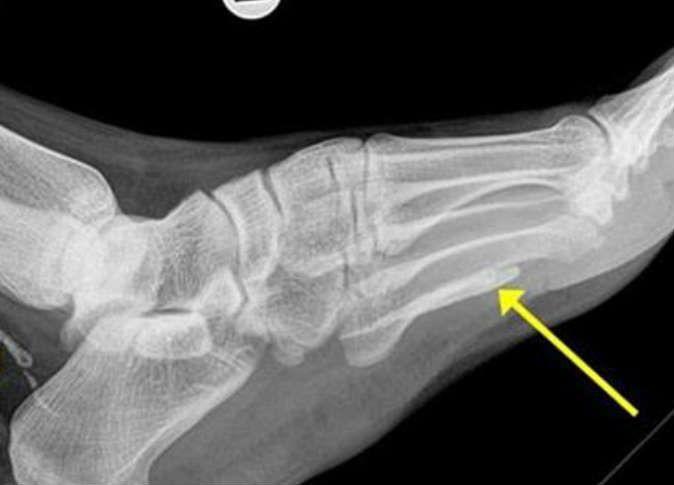

عثر أطباء على دودة طولها متر تقريباً مستقرة في قدم سوداني مهاجر مقيم في أستراليا، ظلت تتغذى على لحمه لأكثر من 4 سنوات.

وشعر الرجل السوداني "38 عاماً" الذي توجه إلى ملبورن للاستقرار هناك، بتورم قدمه وكاحله بعد آلام استمرت معه لعام تقريباً، فزار الطبيب، ليظهر للأخير في الأشعة السينية التي أجراها المريض وجود دودة طولها متر، حسبما ذكرت صحيفة دايلي ميل البريطانية.

وقام الأطباء بتحليل الدودة، فتبين أنها كانت مستقرة في منطقتي الكاحل والقدم على شكل قطعتين لولبيتين لأكثر من 4 سنوات، مشيرين إلى أنها ماتت بعدما تغذت على لحم القدم وبدأت في التحلل داخل جسم الرجل، محدثة له تورماً وقروحاً.

وأوضح الطبيب المعالج د. داربي أن الدودة التي عُثر عليها هي "دودة غينيا" وهي دودة خيطية طويلة رفيعة تعيش تحت الجلد وتسبب قروحاً مؤلمة.

يُشار إلى أن هذا النوع من الديدان موجود في جنوب السودان وإثيوبيا وغانا وتشاد، لكنها في الوقت ذاته ليست معدية، إذ لا تنتقل إلى شخص آخر.